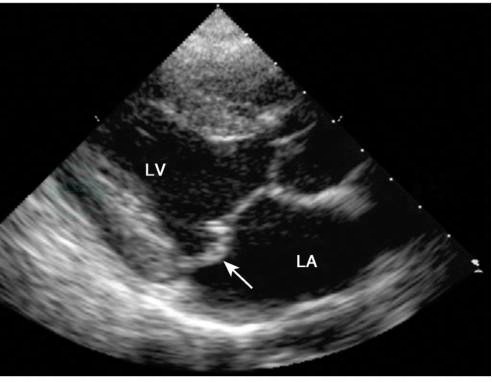

有特征性改变,可观察二尖瓣脱垂的程度、瓣叶形态、瓣环大小、腱索长短粗细、左心房和左心室的大小,可测定心功能和肺动脉压力等,是目前检查二尖瓣脱垂最具有决定性的无创伤性方法。如两个瓣叶均有脱垂,在M型超声心动图上前瓣叶曲线在CD段后突成弧形,后瓣叶曲线则有更大的后突,两瓣叶曲线在该处分离。二维超声心动图胸骨旁长轴切面上可看到二尖瓣关闭时,瓣叶超过二尖瓣环水平(图1)。

图1二尖瓣脱垂的二维超声心动图表现